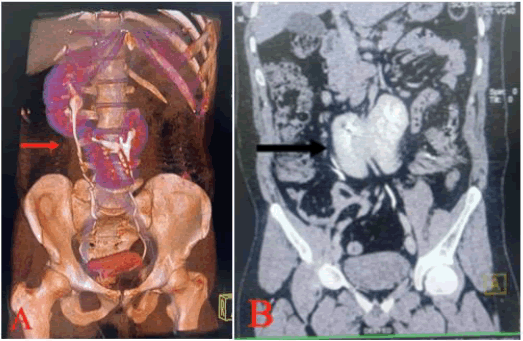

The right kidney showed a malrotated anteriorly faced duplex collecting system, with both ureters draining separately into the urinary bladder. Within the right renal upper collecting pelvis, a calculus with a maximum diameter of 1.5 cm and a mean density of 1000 HU was observed (Figure 3).

The right ureter was normal. Left kidney is in midline, upper pole of left kidney fused with lower pole of right kidney. The patient then decided to have the calculus removed by Percutaneous Nephrolithotomy (PCNL).

Figure 3. 3D computed tomography (A) and CECT KUB (B) revealed left to right crossed-fused renal ectopia